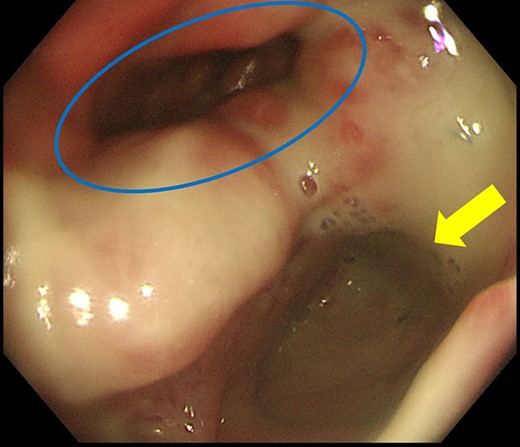

Case 2 was a 58-year-old man with a BMI of 30.3 kg/m2. Robot-assisted LAR and ileostomy was performed for lower rectal cancer over the past 2017 years, and a 1/2 circumferential fistula around the 6 o’clock direction was recognized on postoperative colonoscopy (Fig. 4). The patient was diagnosed as having a grade A anastomotic leakage without symptom because of the anastomotic leakage. He was discharged on POD 26 and was followed up on an outpatient basis. Contrast imaging performed simultaneously with endoscopic examination 6 months after the operation showed remarkable improvement of the abscess cavity, but it still remained (Fig. 5a and b). The anastomotic leakage improved 11 months after surgery (Fig. 6), but a polyp was found on the anal side 2 cm from the anastomotic site and was resected. Adenocarcinoma, pTX, ly0, v0, pHMX, and pVMX were diagnosed. The tumor was followed up because the depth of penetration, the deep stump, and the horizontal stump remained unknown (Fig. 7). Regarding the polypectomy site, no abnormality was found in the examination 8 months after resection of the polyp. Therefore, ileostomy closure was performed 18 months after the first operation (Fig. 8). Postoperatively, it took some time to improve the intestinal movement with paralytic ileus, but the patient was discharged 18 days after surgery. The Wexner score one month after closure was 18 points and still showed high anal dysfunction but the patient was under observation at the outpatient department.

Colonoscopy shows a true lumen (circle) and an abscess cavity (arrow) with drainage of pus.